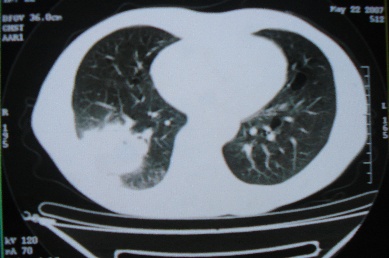

ct10716,男,59岁。发热咳嗽一天,咯血一次入院。

病灶中心有低密度,气体,病灶周围炎性浸润可能为肺脓肿,量体温、查个痰就是了,但肺脓肿一般都多少会有点兄水的。左肺下局部密度减低,小叶中心肺气肿。

病灶边缘较模糊,中心见低密度影及少量气影,宽基与胸膜相连,周围见炎性浸润,考虑右下肺脓肿。

病灶边缘较模糊,中心见低密度影及少量气影,宽基与胸膜相连,周围见炎性浸润,考虑右下肺脓肿。建议治疗后复查。

右下肺病灶,边缘模糊,中心见低密度坏死区及气体影,结合病史较短,以发热为主,考虑右下肺脓肿,建议抗炎治疗后复查。